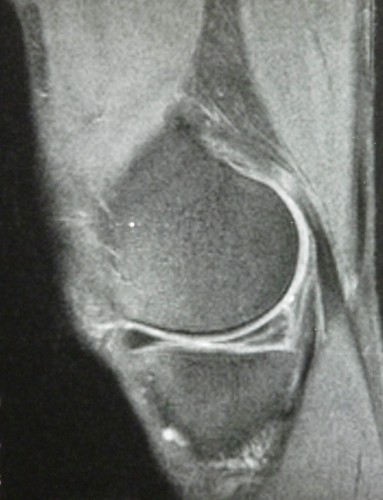

Meniskusriss 2001-1